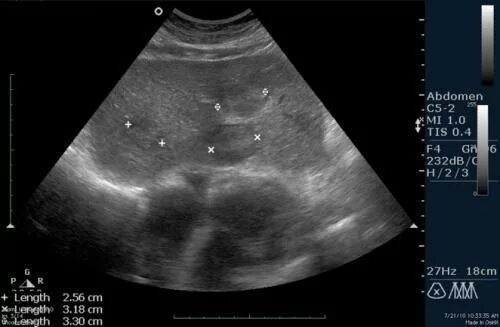

Метастазы в поджелудочную железу прогноз